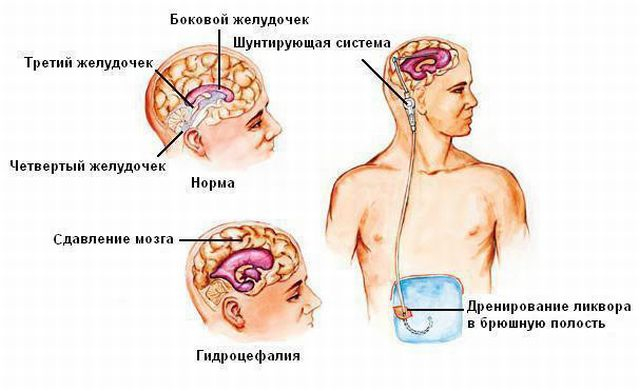

Вентрикуло-перитонеальный шунт: Показания и применение